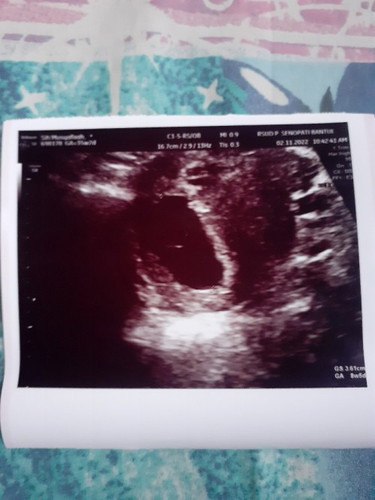

Td saya usg di uk 9w tapi cuma kelihatan kantung nya aja, apa bunda2 ada yg pernah ngalamin ?

Hamil kosong

Usg abdomen atau trans V bun? Kl abdomen kayanya ada yg blm terlihat jg sih